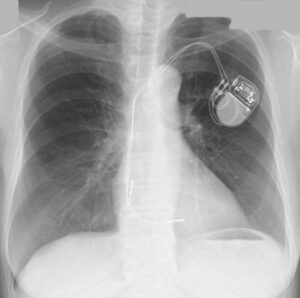

あなたはペースメーカを植え込まれている患者を担当したことがあるでしょうか?下のような胸部レントゲンを見たことがあると思います。